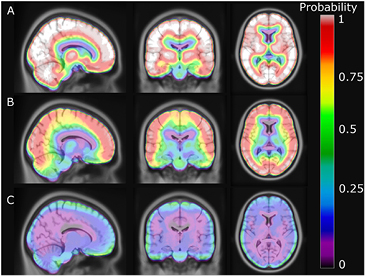

The average error over the full brain was −0.1% (±2.8%), compared to −6.9% (±2.1%) in UTE. The mean absolute error over the full brain was 3.4% (±1.6%), compared to 8.2% (±1.9%) in UTE. The averaged %-difference image from PETCT to PETDIXON, PETUTE and PETRESOLUTE, respectively, is shown in three orientations (figure 6). Notice the error of 10–15% in UTE near the cortex (figure 6(B)). This error is reduced to less than 1% when using RESOLUTE. The results for the averaged joint histograms are shown in figure 7. The values in PETRESOLUTE are closer to PETCT than PETUTE, which is supported by the r2 scores of 0.66 for Dixon, 0.78 for UTE and 0.92 for RESOLUTE. The systematic underestimation compared to PETCT when using Dixon and UTE is significantly reduced when RESOLUTE is applied for MR-AC. A histogram of errors can be seen in supplementary figure 1 (stacks.iop.org/PMB/60/8047/mmedia). We saw an improvement of our method over UTE and Dixon, as the number of voxels greater than ±5% was significantly reduced and the number of voxels around 0% error was increased. The systematic negative bias observed in UTE and DIXON was also considerably reduced.

Figure 6. Averaged %-difference images of 154 patients. (A) shows Dixon, (B) UTE and (C) shows RESOLUTE. Notice that errors of less than −15% are clamped to cyan in A and B.

Figure 8. Probability of error greater than ±5% for each voxel. (A) shows Dixon, (B) UTE and (C) shows RESOLUTE.

An image showing the voxel-wise fraction of errors greater than ±5% is presented in figure 8. The probability of having errors greater than ±5% at the cortex is more than 90% when using UTE but only 10–25% when using our method. The probability of an error at the frontal sinus and in the cerebellum is also significantly reduced. Using RESOLUTE, the average fraction of the brain within ±10% and ±5% from PETCT was 95% and 77%, respectively (table 2). In comparison, Dixon/UTE gave 37%/72% within ±10% and 7%/28% within ±5%. The ROI based comparison is presented in figure 9. Using our method, the average error was below −1.2% in all regions of the brain, including the cerebellum, which is often confounded by complex air/tissue interfaces for the regions in the vicinity.